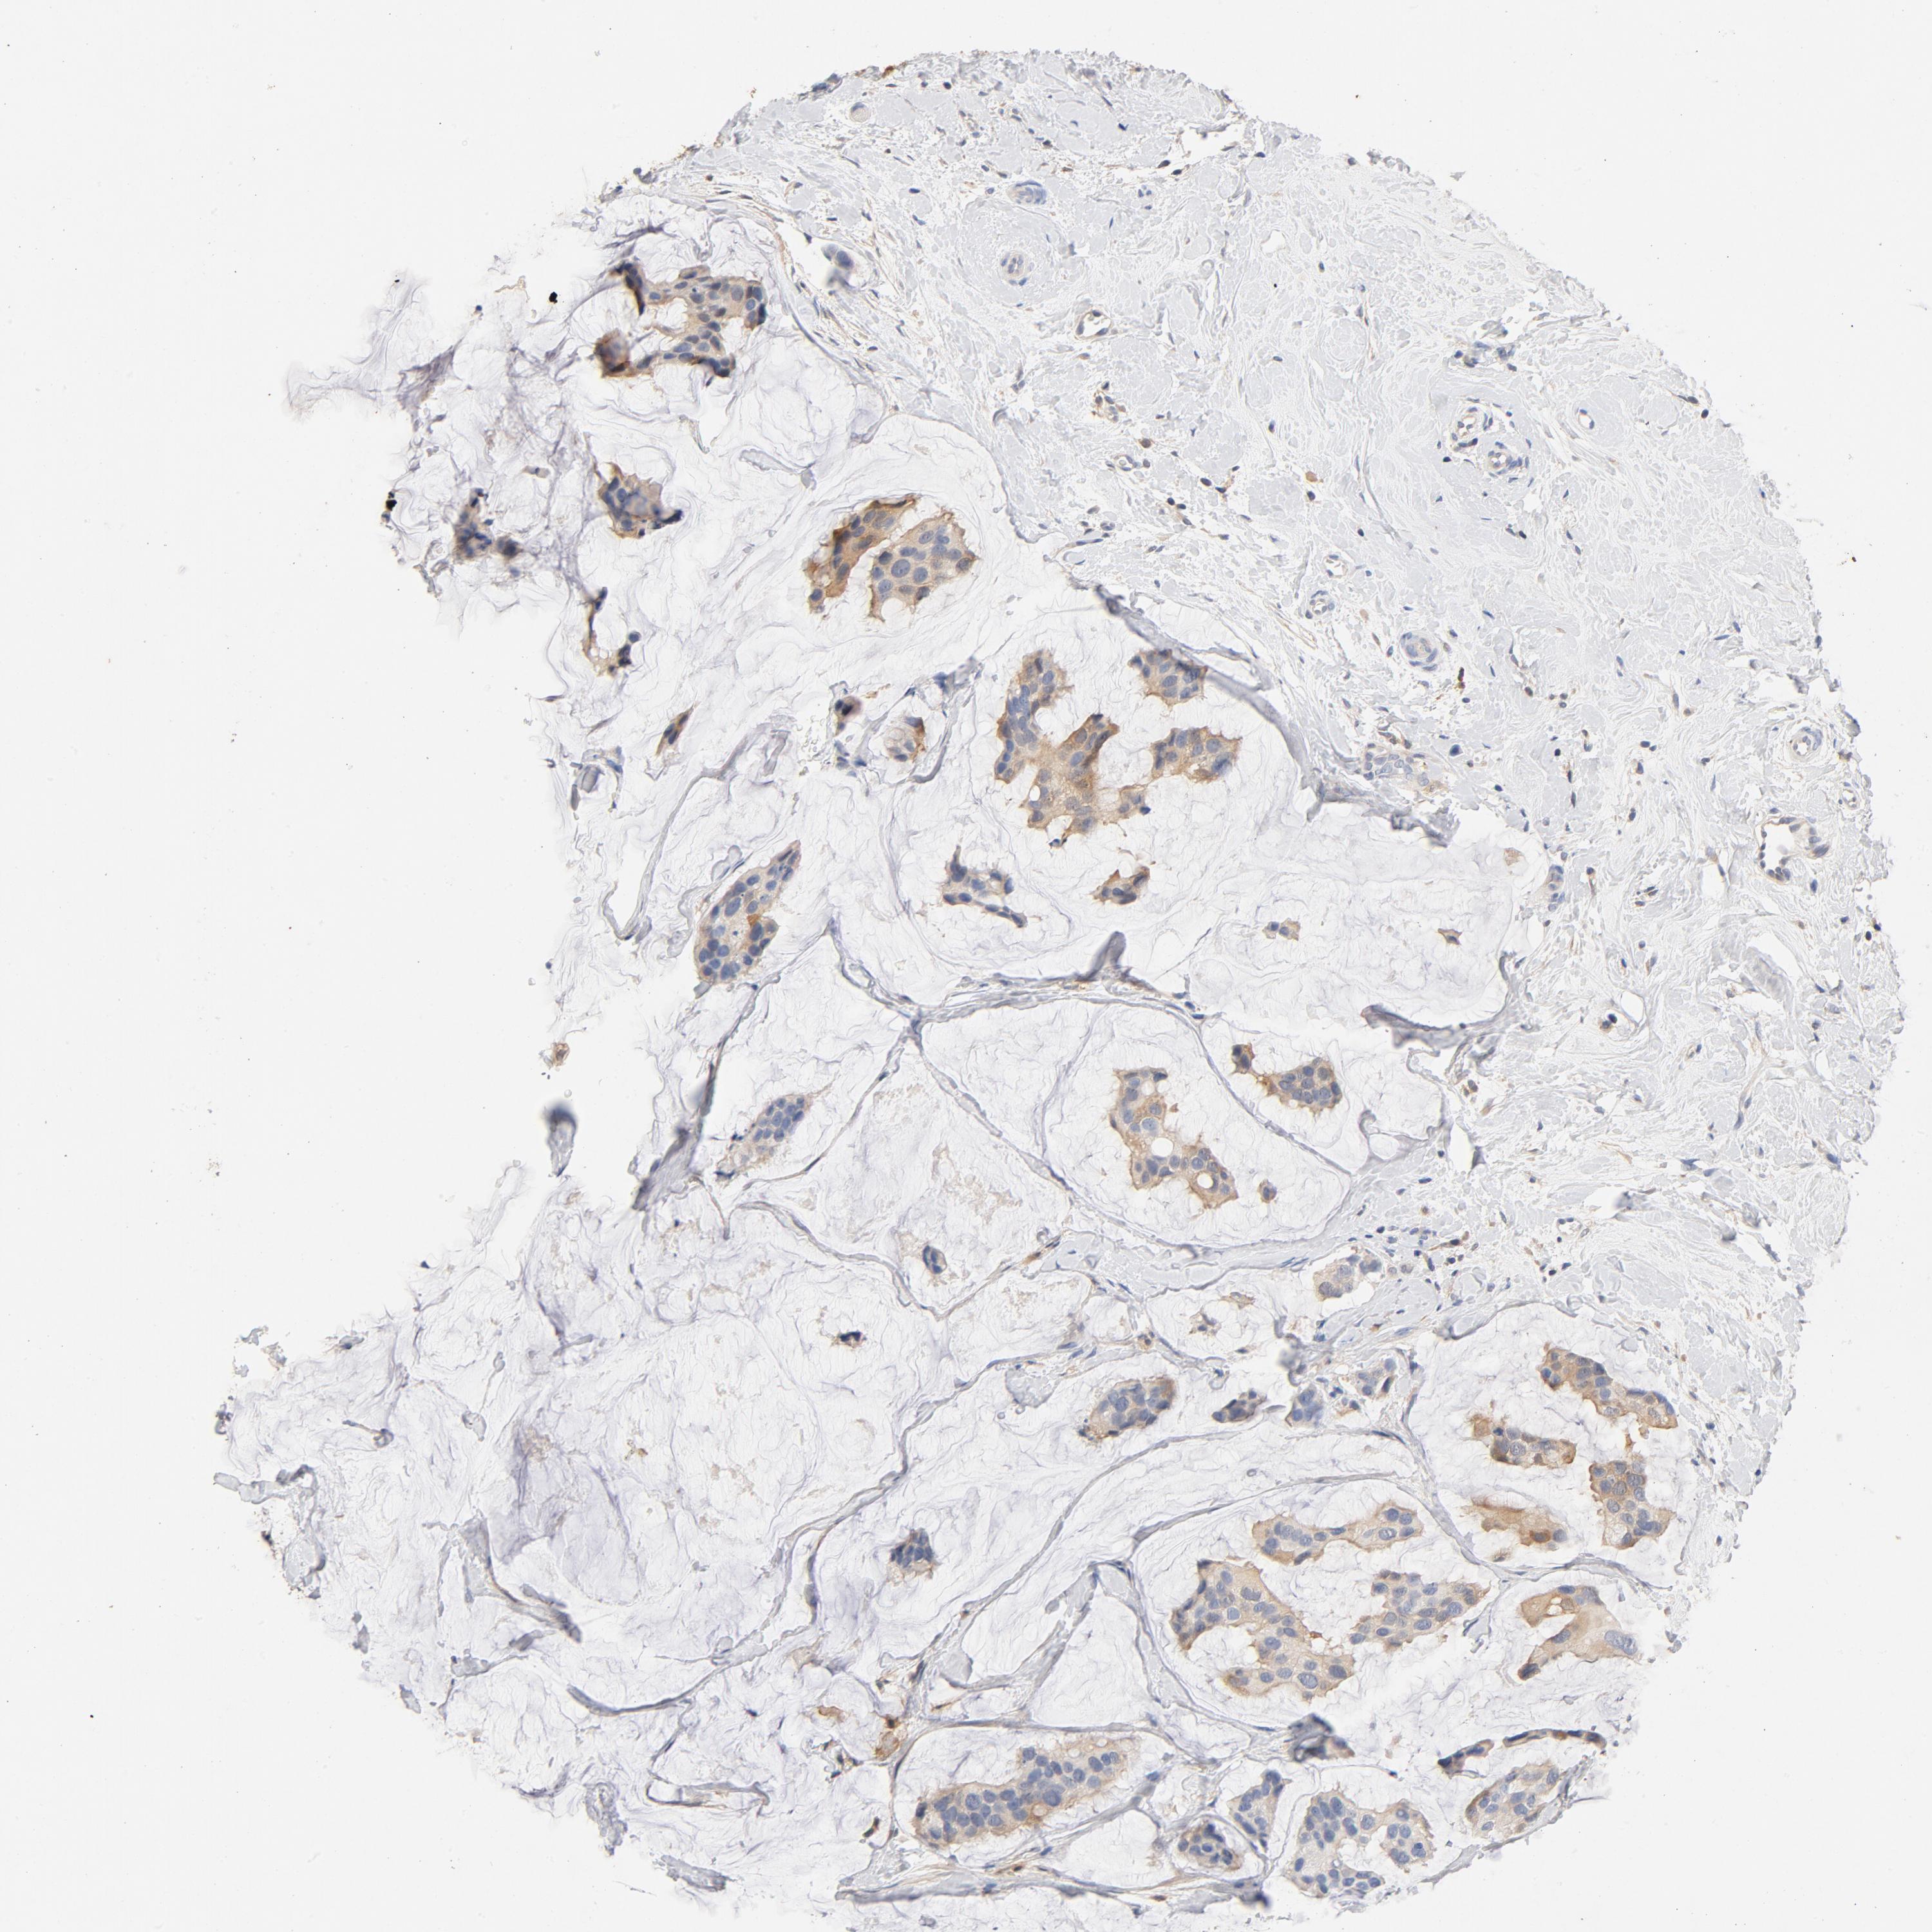

CANCER BREAST CANCER Show tissue menu

BRCA TCGA BRCA VALIDATION PROTEIN EXPRESSION

Breast cancer

Human cancer